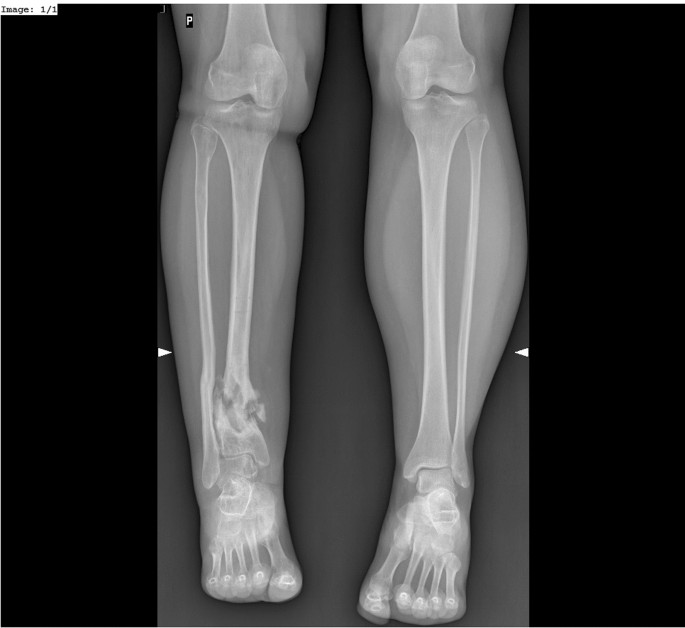

Nonunions of the tibia, particularly those located in the distal third of the bone, are relatively common in clinical practice1,2,3,4. Despite of this, they pose a serious therapeutic challenge for orthopedic surgeons1,2,3,5,6,7,8,9,10,11,12,13,14. Nonunions of the tibia may be associated with: low-density bone tissue, bone loss, adjacent soft-tissue damage, limb shortening, limb deformities, and joint contractures (Fig. 1). All of these adversely affect the course of treatment and increase the risk of treatment failure1,2,3,4,5,7,8,9,10,11,12,13,14,15,16,17,18,19,20,21,22. In nonunions of the tibia, the Ilizarov method helps achieve bone union, eliminate possible infections, equalize limb length, and correct any deformities that may have developed over the course of treatment1,2,3,4,5,7,8,9,10,11,12,13,14,15,17,18,19,21,22.

The purpose of our study was to assess the results of treatment with the Ilizarov method in patients with aseptic nonunions of the tibia, depending on the employed treatment strategies and surgical techniques (Figs. 2, 3).